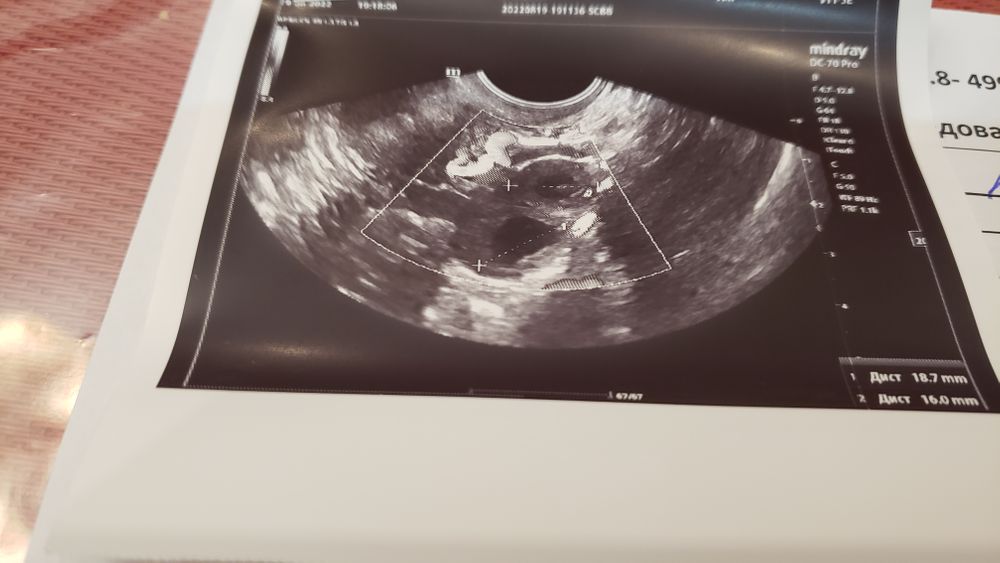

Кристина, причина моих болей двойная овуляция в одном яичнике.

Врач сказал, если не будет цикла-приходи.😂😂А хгч - говорит не показатель, рано.